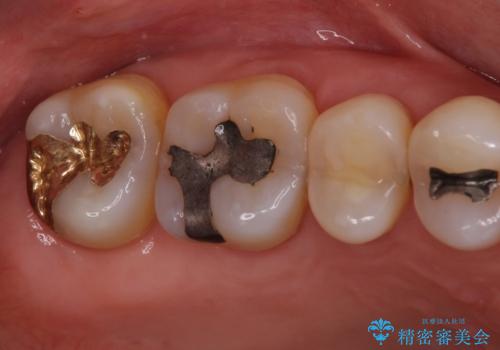

- 奥歯に装着されてい銀歯の中が虫歯になってしまったとのことで来院された患者様です。

虫歯をしっかりと取り除き、ゴールドインレー(PGAインレー)にて修復することとしました。